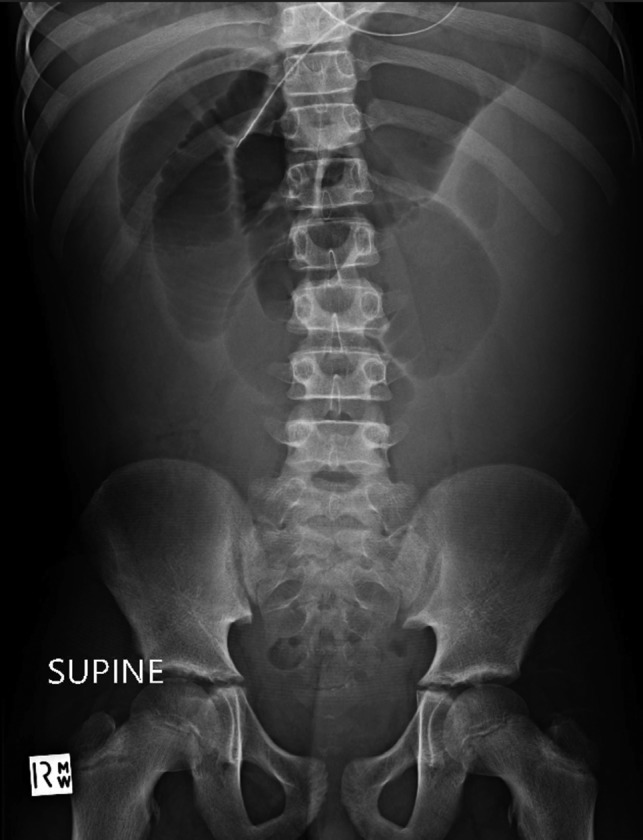

Figure 3:

Supine abdominal radiograph on day 5 showing dilated small bowel loops with no bowel gas evident in the colon.